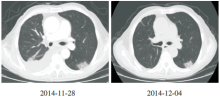

郑明英:患者在2014-10-24复查PET-CT示右肺动脉栓塞, 见图3; 放疗过程中出现频繁的恶心、呕吐, 伴咳嗽、咳痰, 查体:右下肺呼吸音减低, 11月28日复查胸部CT示:右侧胸腔积液较前增多, 左下肺出现斑片影; 胸腔积液找到腺癌细胞, 见图4。2014-11-28至2014-12-04 予抗感染治疗:头孢哌酮/舒巴坦 2.25g q8h, 2014-12-04复查胸部CT示左下肺斑片影无明显改变, 见图5; 请放射科医生重新评估胸部CT发现左肺动脉栓塞, 左下肺斑片影考虑肺栓塞造成。2014-12-12予患者GC方案化疗。